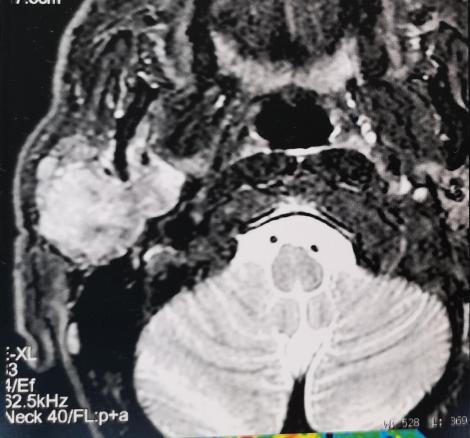

Dr Lanciaux-Lemoine, chirurgie maxillo-faciale, CHU Pitié-Salpêtrière, La Revue du Praticien IRM, coupe axiale, séquence T2, lésion parotidienne arrondie en hypersignal T2.